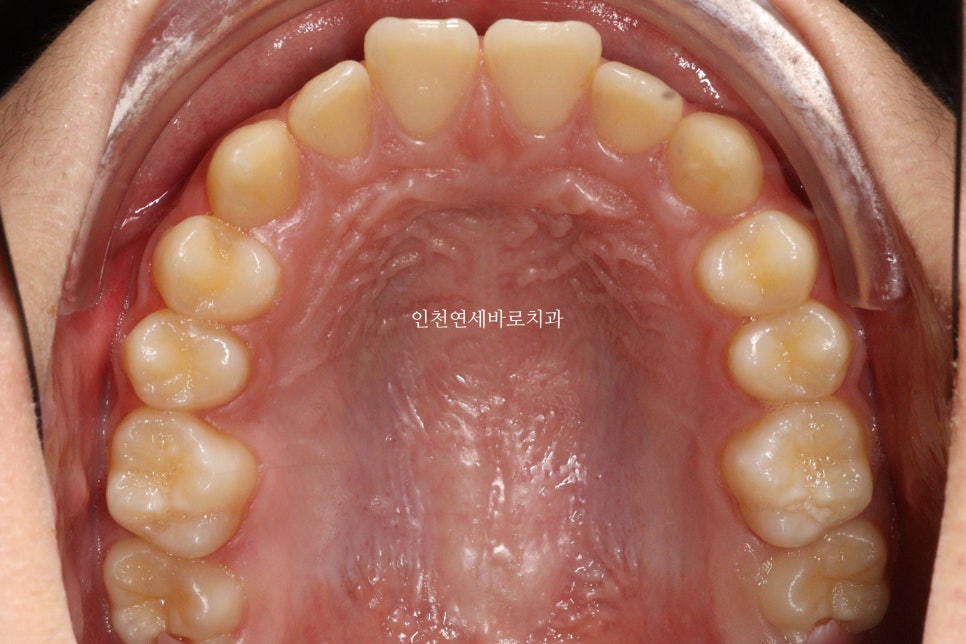

치료 전과 후 입니다.

앞니가 후방이동 한것이 확인됩니다.

우리는 부분교정을 한것이 아니라 간단한 전체교정을 한것입니다.